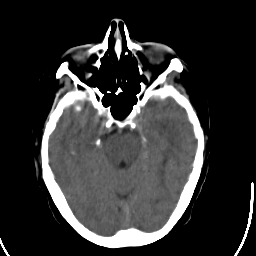

Stroke CT #1 -- Slice #8

[Home][Help][Clinical] Slice 8